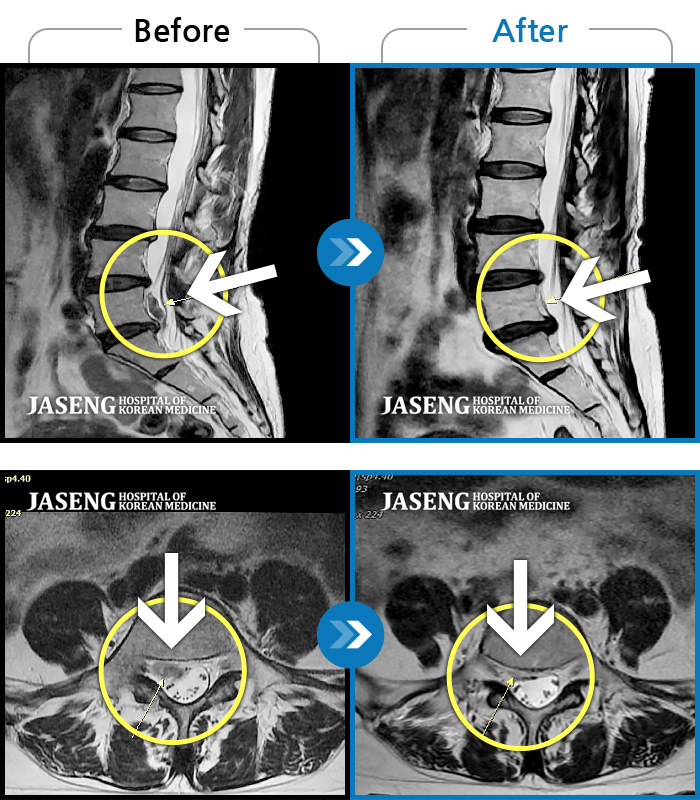

허리디스크

울산 · 정운석 원장

우측 하요추부 통증-우측 둔부-소퇴 후면 통증/비증

촬영시기

2021.08.08 ~ 2021.08.13

2021.08.20